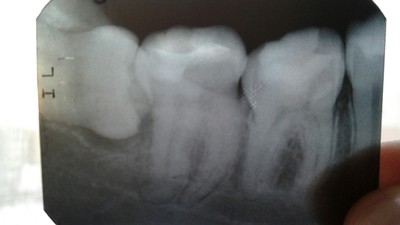

Удаление подобных зубов можно назвать более простым случаем по сравнению с другими, но только лишь в том случае, если у зуба один прямой корень. Тогда удаление может пройти достаточно быстро. Но такие клинические случаи встречаются крайне редко. И, посмотрев на снимок, мы видим крючья, а не корни, которые при должном давлении, могут просто сломаться. Корней обычно 2, и в таком случае нам просто нужно отделить один корень от другого при помощи все того же инструмента — «повышающего» наконечника . И аккуратно каждый из корней достать по отдельности. Начало и завершение удаления таких зубов такое же, как и у всех остальных.